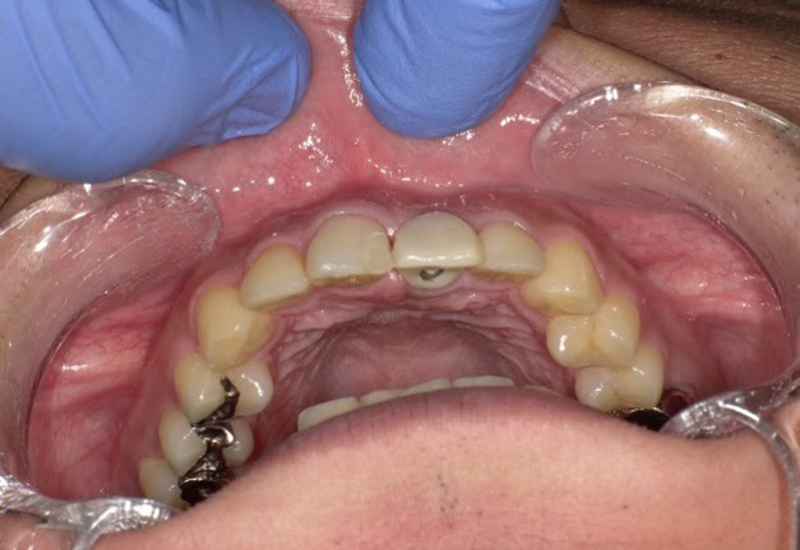

術後3ヶ月に仮歯を入れています。

![]() |